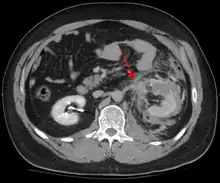

The imaging modality of choice is contrast-enhanced, computed tomography (CT) which is readily available in most emergency departments of moderate or above size. Scan times have become shorter with each generation of scanners and current scans are quick and accurately demonstrate renal injuries together with associated injuries to other abdominal or retroperitoneal organs.

Unlike ultrasound examination (FAST), CT provides anatomic and functional information that allows for accurate grading of the injury which is partly responsible for a growing trend toward conservative management (intravenous fluids, close monitoring, watchful waiting) of renal trauma.[8] Conservative management does not apply in situations where extensive urinary extravasation or devitalized areas of renal parenchyma are found and especially if associated with injuries to other abdominal organs; these cases are complication-prone and much more likely to require surgery. That being said, a retrospective study suggests that primary conservative treatment of blunt kidney rupture seems to lead to less surgery, especially less open surgery, and less blood and renal parenchyma loss, compared to a strategy of initial surgery.[9]